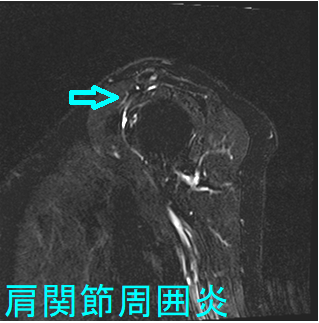

肩関節周囲炎とは肩・肩周囲の炎症で、中年に起こり易いため五十肩と呼ばれます。初期には肩関節を動かしても動かさなくても痛み、特に夜間の痛みが強くなります。数か月-数年で、肩関節を動かしにくくなり、服を着替えるにも困難が生じます。

五十肩は学術的な病名ではなく、国際的には癒着性関節包炎(adhesive capsulitis)や凍結肩(frozen shoulder)と呼ばれます。

肩関節周囲炎(癒着性関節包炎・凍結肩)は、糖尿病や甲状腺疾患との関連が強い[Am Fam Physician. 2008 Feb 15;77(4):453-60.]。

糖尿病の10%から20%に五十肩(肩関節周囲炎・凍結肩・癒着性関節包炎)が発病するとされますが、その原因は不明です。甲状腺ホルモンは、骨、軟骨、腱に影響するため、甲状腺機能低下症・甲状腺機能亢進症も、五十肩の発病に関連あるとされます。(J Biol Regul Homeost Agents. 2016 Jul-Sep;30(3):867-870.)(Arthritis Rheum. 1987 Aug;30(8):936-9.)

甲状腺機能低下症の重症度と、五十肩(肩関節周囲炎・凍結肩・癒着性関節包炎)の重症度に相関が認められます。(J Shoulder Elbow Surg. 2017 Jan;26(1):49-55.)

潜在性甲状腺機能低下症や糖尿病は、肩関節手術後に生じる肩のこわばり(手術が無効になる状態)の危険因子とされます(Knee Surg Sports Traumatol Arthrosc. 2017 Jul;25(7):2208-2216.)

甲状腺機能低下症により上腕二頭筋腱長頭部が自然断裂した症例が報告されています(J Med Case Rep. 2016 Jan 13;10:2.)。甲状腺機能低下症による腱炎は、通常の腱炎より治療抵抗性とされます。腱炎は甲状腺機能低下症の徴候的な症状で、甲状腺機能が改善すると腱炎症状も軽減します。